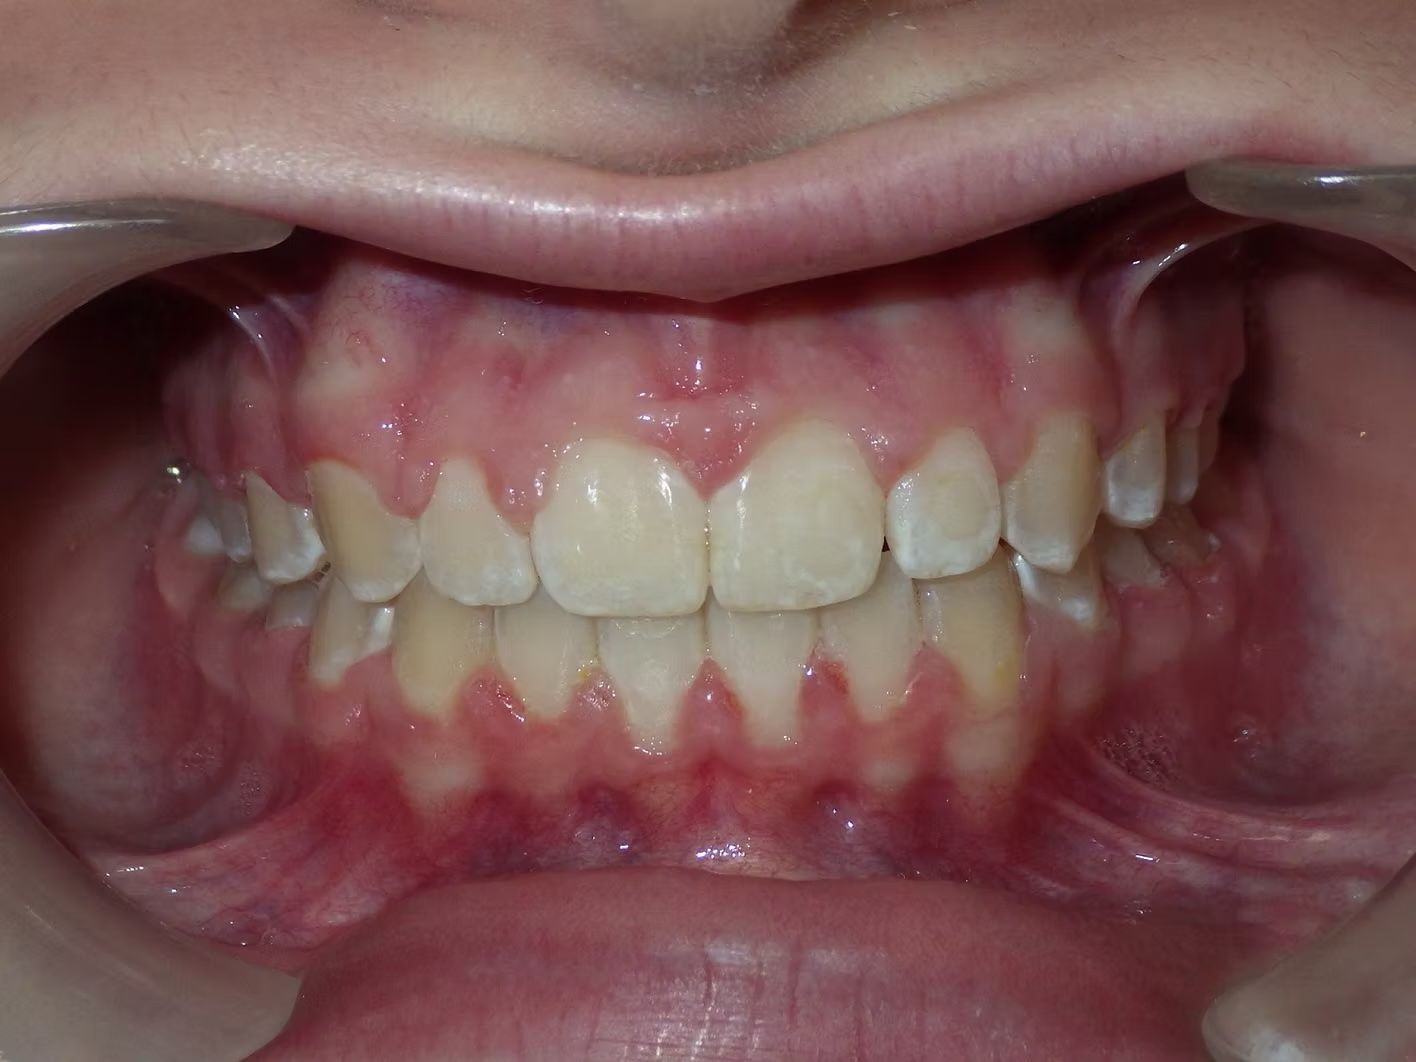

BRIANNA

Brianna's lower left 1st premolar was completely in a brodie bite (outside the normal arch) and her top and bottom teeth were very crowded. Dr. Freedman corrected her bite and crowding without removing any teeth.